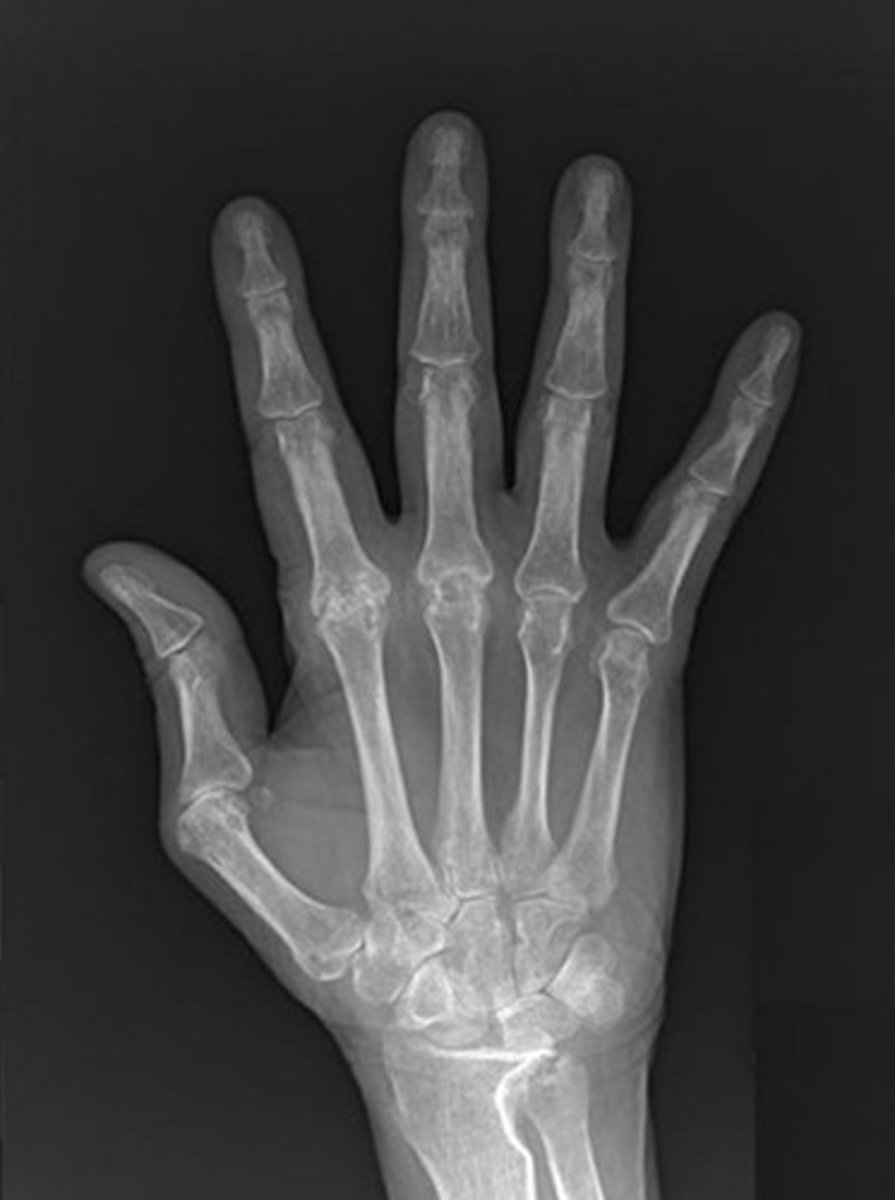

XR: uniform joint space narrowing, erosions

XR: sclerosis, osteophytes, decreased joint space

what are the XR findings for psoriatic arthritis?

osteolysis, pencil-in-cup deformity, sacroilitis, relative lack of osteoporosis